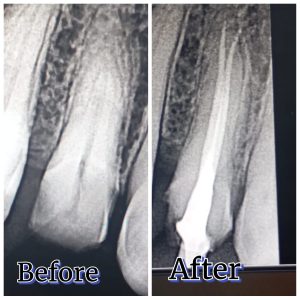

A root canal Treatment (RCT) is a specialized dental procedure that removes infected or dead pulp tissue from inside a tooth. The canal is then cleaned, disinfected, and sealed with biocompatible material to preserve the natural tooth structure.

| Digital X-ray | We use a high-resolution dental X-ray to precisely locate the infected tooth area before starting the root canal treatment at Bright Smile Dental clinic Faisalabad. |

| Obturation & Filling | We fill and seal the canals with biocompatible material (Obturation) to ensure long-term protection. |